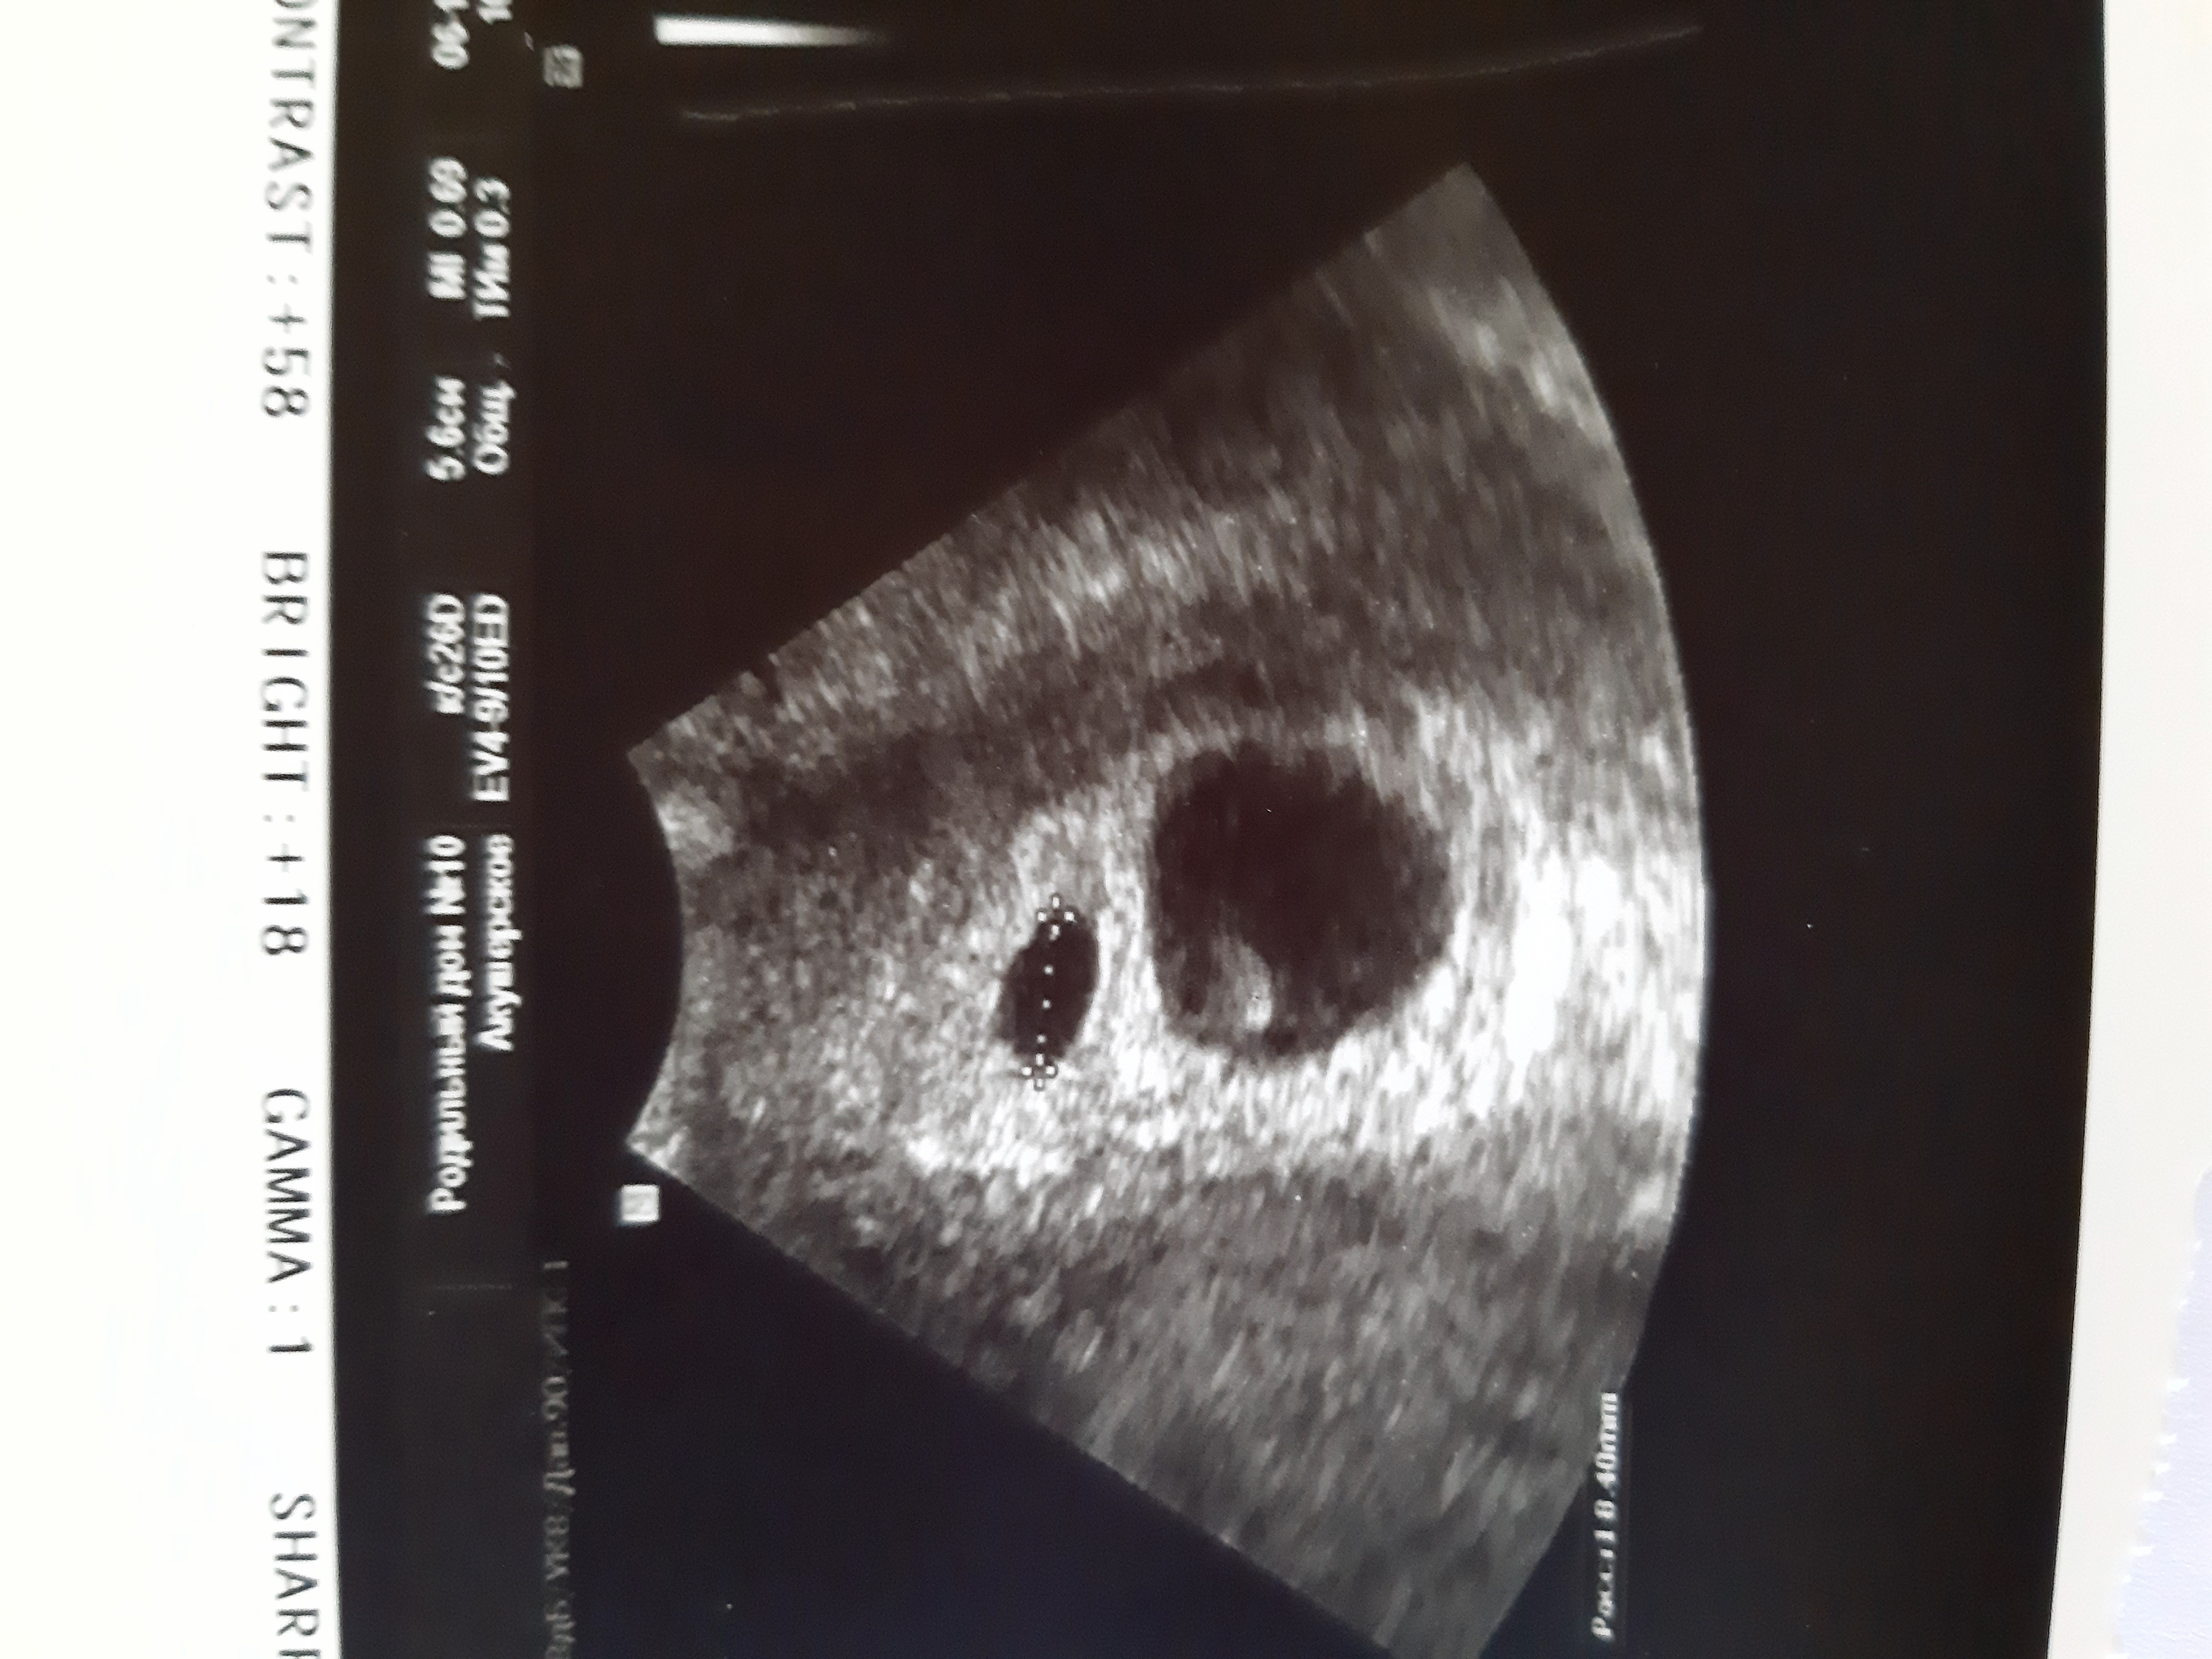

Девочки, я дура. Муж попал в аварию,я очень переживала и плакала несколько дней. Просто не могла успокоится. Сходила на узи ,а там из-за стрессовой ситуации у ребёночка расширился правый боковой желудочек в голове( вентрикуломегалия). Я идиотка прост...